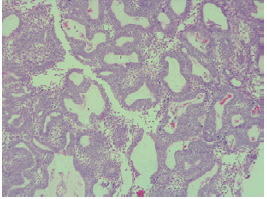

Biopsy was performed on the lesion of the scalp revealing ameloblastoma metastases; the subject was taken to surgery with wide local excision and free flap reconstruction. Surgical specimen pathology confirmed metastatic ameloblastoma and reported tumor-free section borders with margins of 14mm (Figure 2).

Follicular cystic ameloblastoma and plexi-form ameloblastoma were identified in all the pathologies analyzed since the initial biopsy and in the different surgical specimens (Figures 3 and 4), both from the local resections and the scalp lesion. No genetic profile of BRAFV600E mutation was performed, since it was not requested during the period when the samples were processed and it is not a routine test performed in the institution.

The pathological types of this disease can be varied: solid, multicystic, unicystic, desmoplastic and peripheral ameloblastoma. 15,16 Solid and multicystic ameloblastomas have been identified as the most aggressive subtype, with a high rate of recurrence after local excision. 17 The most common histological type is the follicular, followed by the plexiform; other histological types are the acanthomatous, granular and basaloid. 1 The case presented here had a histopathological diagnosis of follicular and plexiform ameloblastoma, which is the most frequently reported. 1